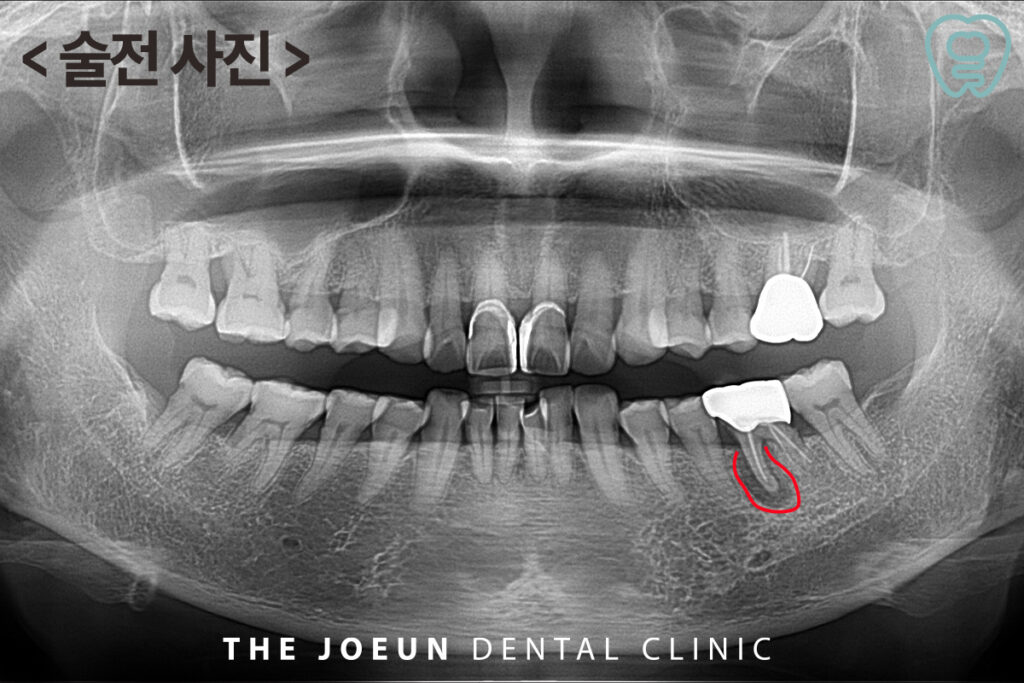

환자분께서는 오래 전 씌워둔 왼쪽 아래 어금니 부위가 씹을 때 힘이 들어가지 않고 잇몸이 붓는 느낌이 있으시다며 내원해 주셨는데요. 파노라마 촬영 시, 왼쪽 아래 첫번째 큰 어금니 뿌리에 커다란 염증이 관찰되었고 이미 치료가 되어 있는 상황이라 발치 후 임플란트 치료를 설명드린 후 진행하기로 하였습니다.

발치 후 치아 뿌리에 붙여 있는 염증 덩어리가 명확히 확인되었는데요. 잇몸뼈의 골질이 약하다고 판단되어 임플란트 식립 후 충분한 기간을 기다려준 뒤 최종 보철물을 진행하는 것으로 하였습니다.